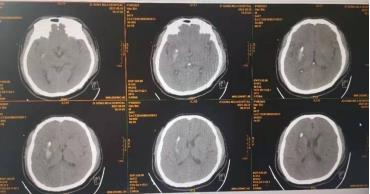

韩先生因突发头痛、左上肢无力被家属紧急送到自贡市第四人民医院神经外科抢救。到医院时,患者双侧瞳孔不等大、对光反应迟钝,左侧肢体对刺痛无反应,颅脑CT显示为右侧基底节区出血。为了给予韩先生及时有效的治疗,尽快的解除血肿对神经纤维传导束的压迫,自贡市第四人民医院神经外科团队将韩先生的数据导入计算机,为其重建面部、颅骨、脑组织及血肿的3D模型,精准计算出了血肿量,计算机设计了最优穿刺入路。在做好充分的术前准备后,神经外科团队在全麻下为韩先生行了3D导板导航下右侧脑血肿引流术,通过3D打印技术制作的手术导板,精准穿刺到达血肿中心位置,顺利地完成手术。手术后复查CT时发现,韩先生的颅内血肿基本被清除。目前,韩先生已康复出院。

术后复查CT血肿基本清除